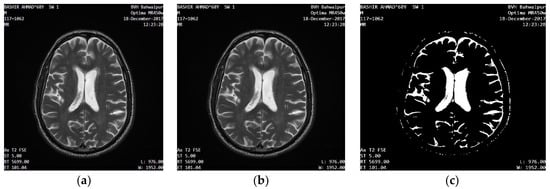

2.2.2. Bitmap Conversion

2.2.3. Noise Removal

2.2.4. Grayscale Conversion